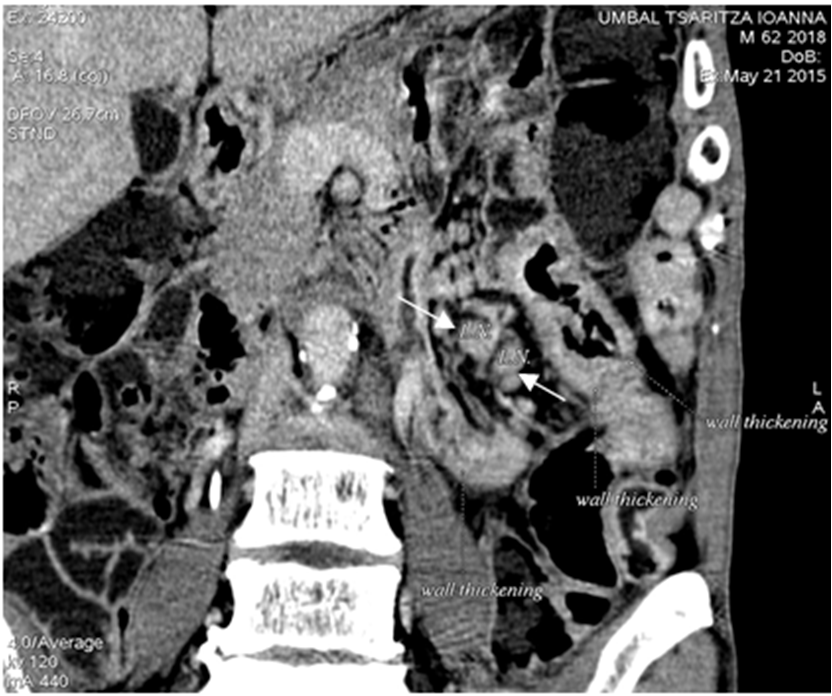

Figure 3. CT enterography Two enlarged mesenteric lymph nodes (white Crohn's Disease Lymph Nodes O’brien cl, pavli p, gordon dm, et al. The system moves lymph, a clear fluid containing white blood cells, through your bloodstream. Detection of bacterial dna in lymph nodes of crohn's disease patients using high throughput sequencing. Detection of bacterial dna in lymph nodes of crohn’s disease patients using high throughput sequencing. Differentiating between intestinal tuberculosis (itb) and crohn's disease. Crohn's Disease Lymph Nodes.